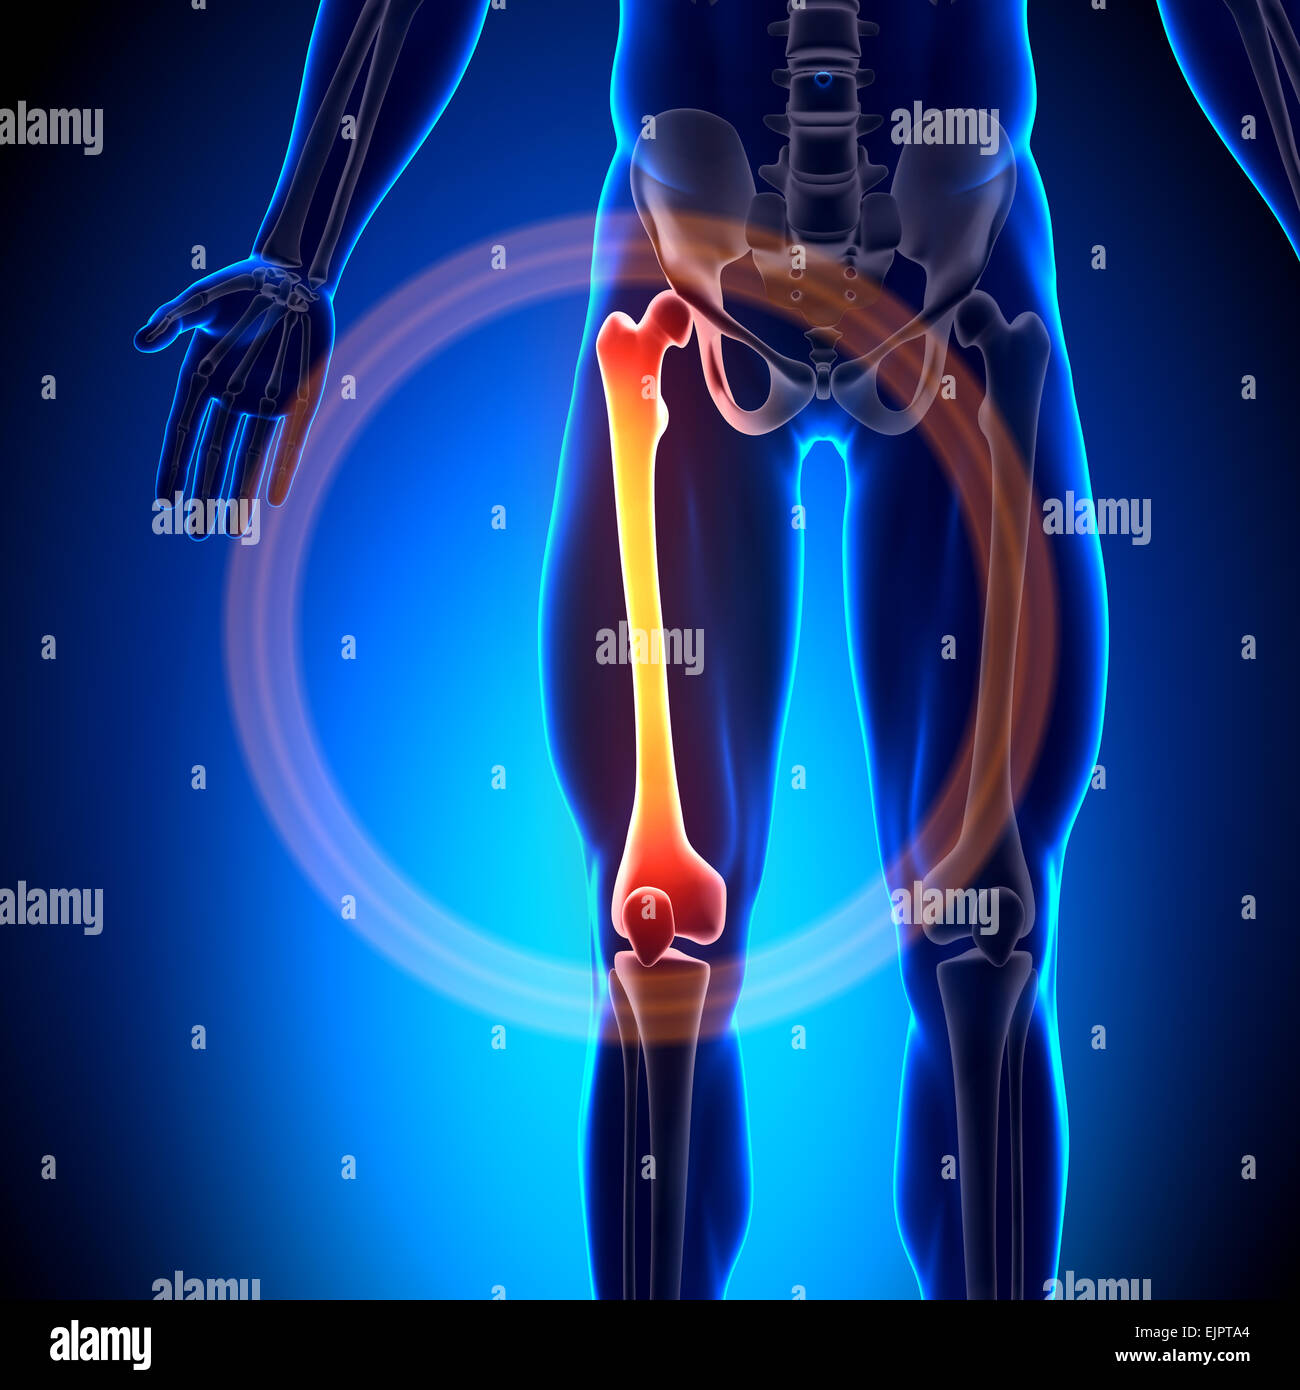

RFWW2CNW–Die männliche Anatomie, Gliedmaßen und hip Muskel- und Skeletterkrankungen Systeme, mit interner Muskelschichten. Vorder- und Rückansicht. schwarzen Hintergrund. 3d-Abbildung.